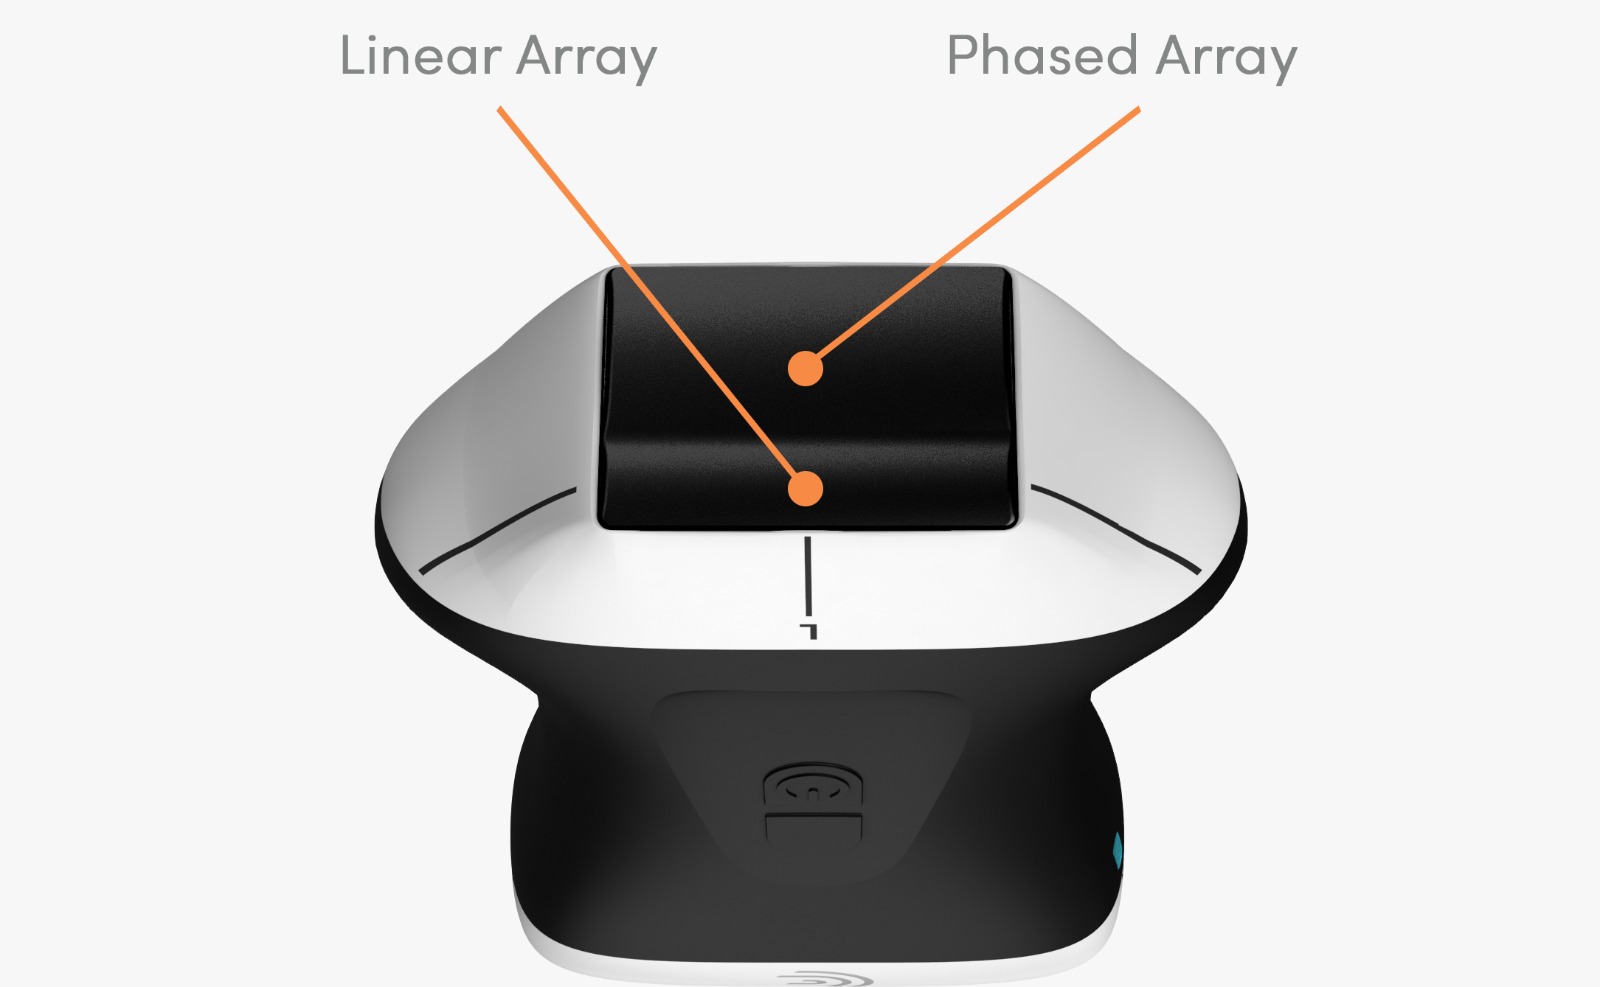

Ecograf Doppler Color Clarius PA HD3 – wireless ultraportabil – Vancouver, Canada (abonament inclus 3 ani)

Sondă phased array cu domeniul de frecvență între 1-5 Mhz, adâncimea de scanare reglabilă între 3-40 cm. Moduri de lucru disponibile: B, M, PW, CDFI și Power Doppler. Pachete de măsurători incluse: Cardiac, Abdomen, OB/GYN, Vezică, Plămân, Superficial.